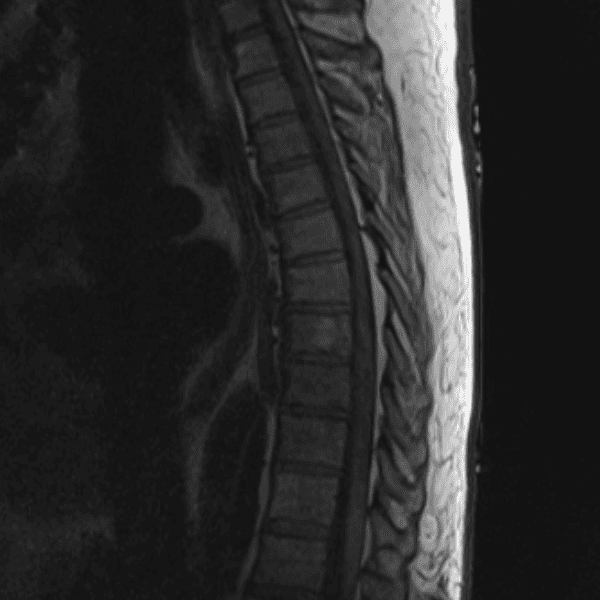

Simulates call by including subtle or difficult cases and some normals.

35 cases